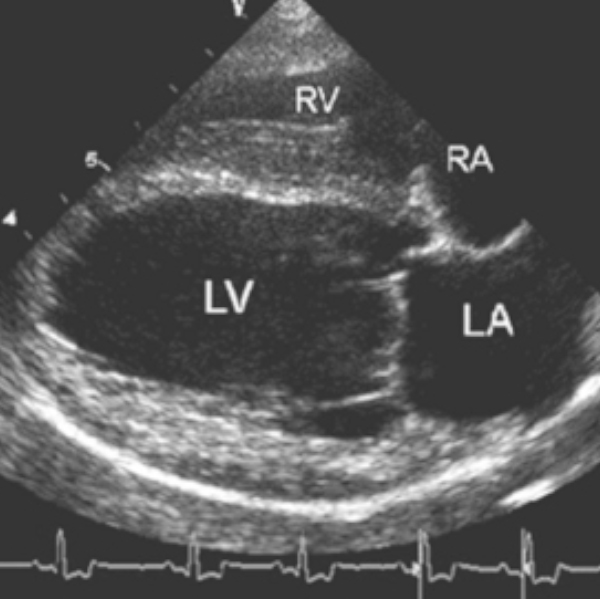

Cardiac Ultrasound